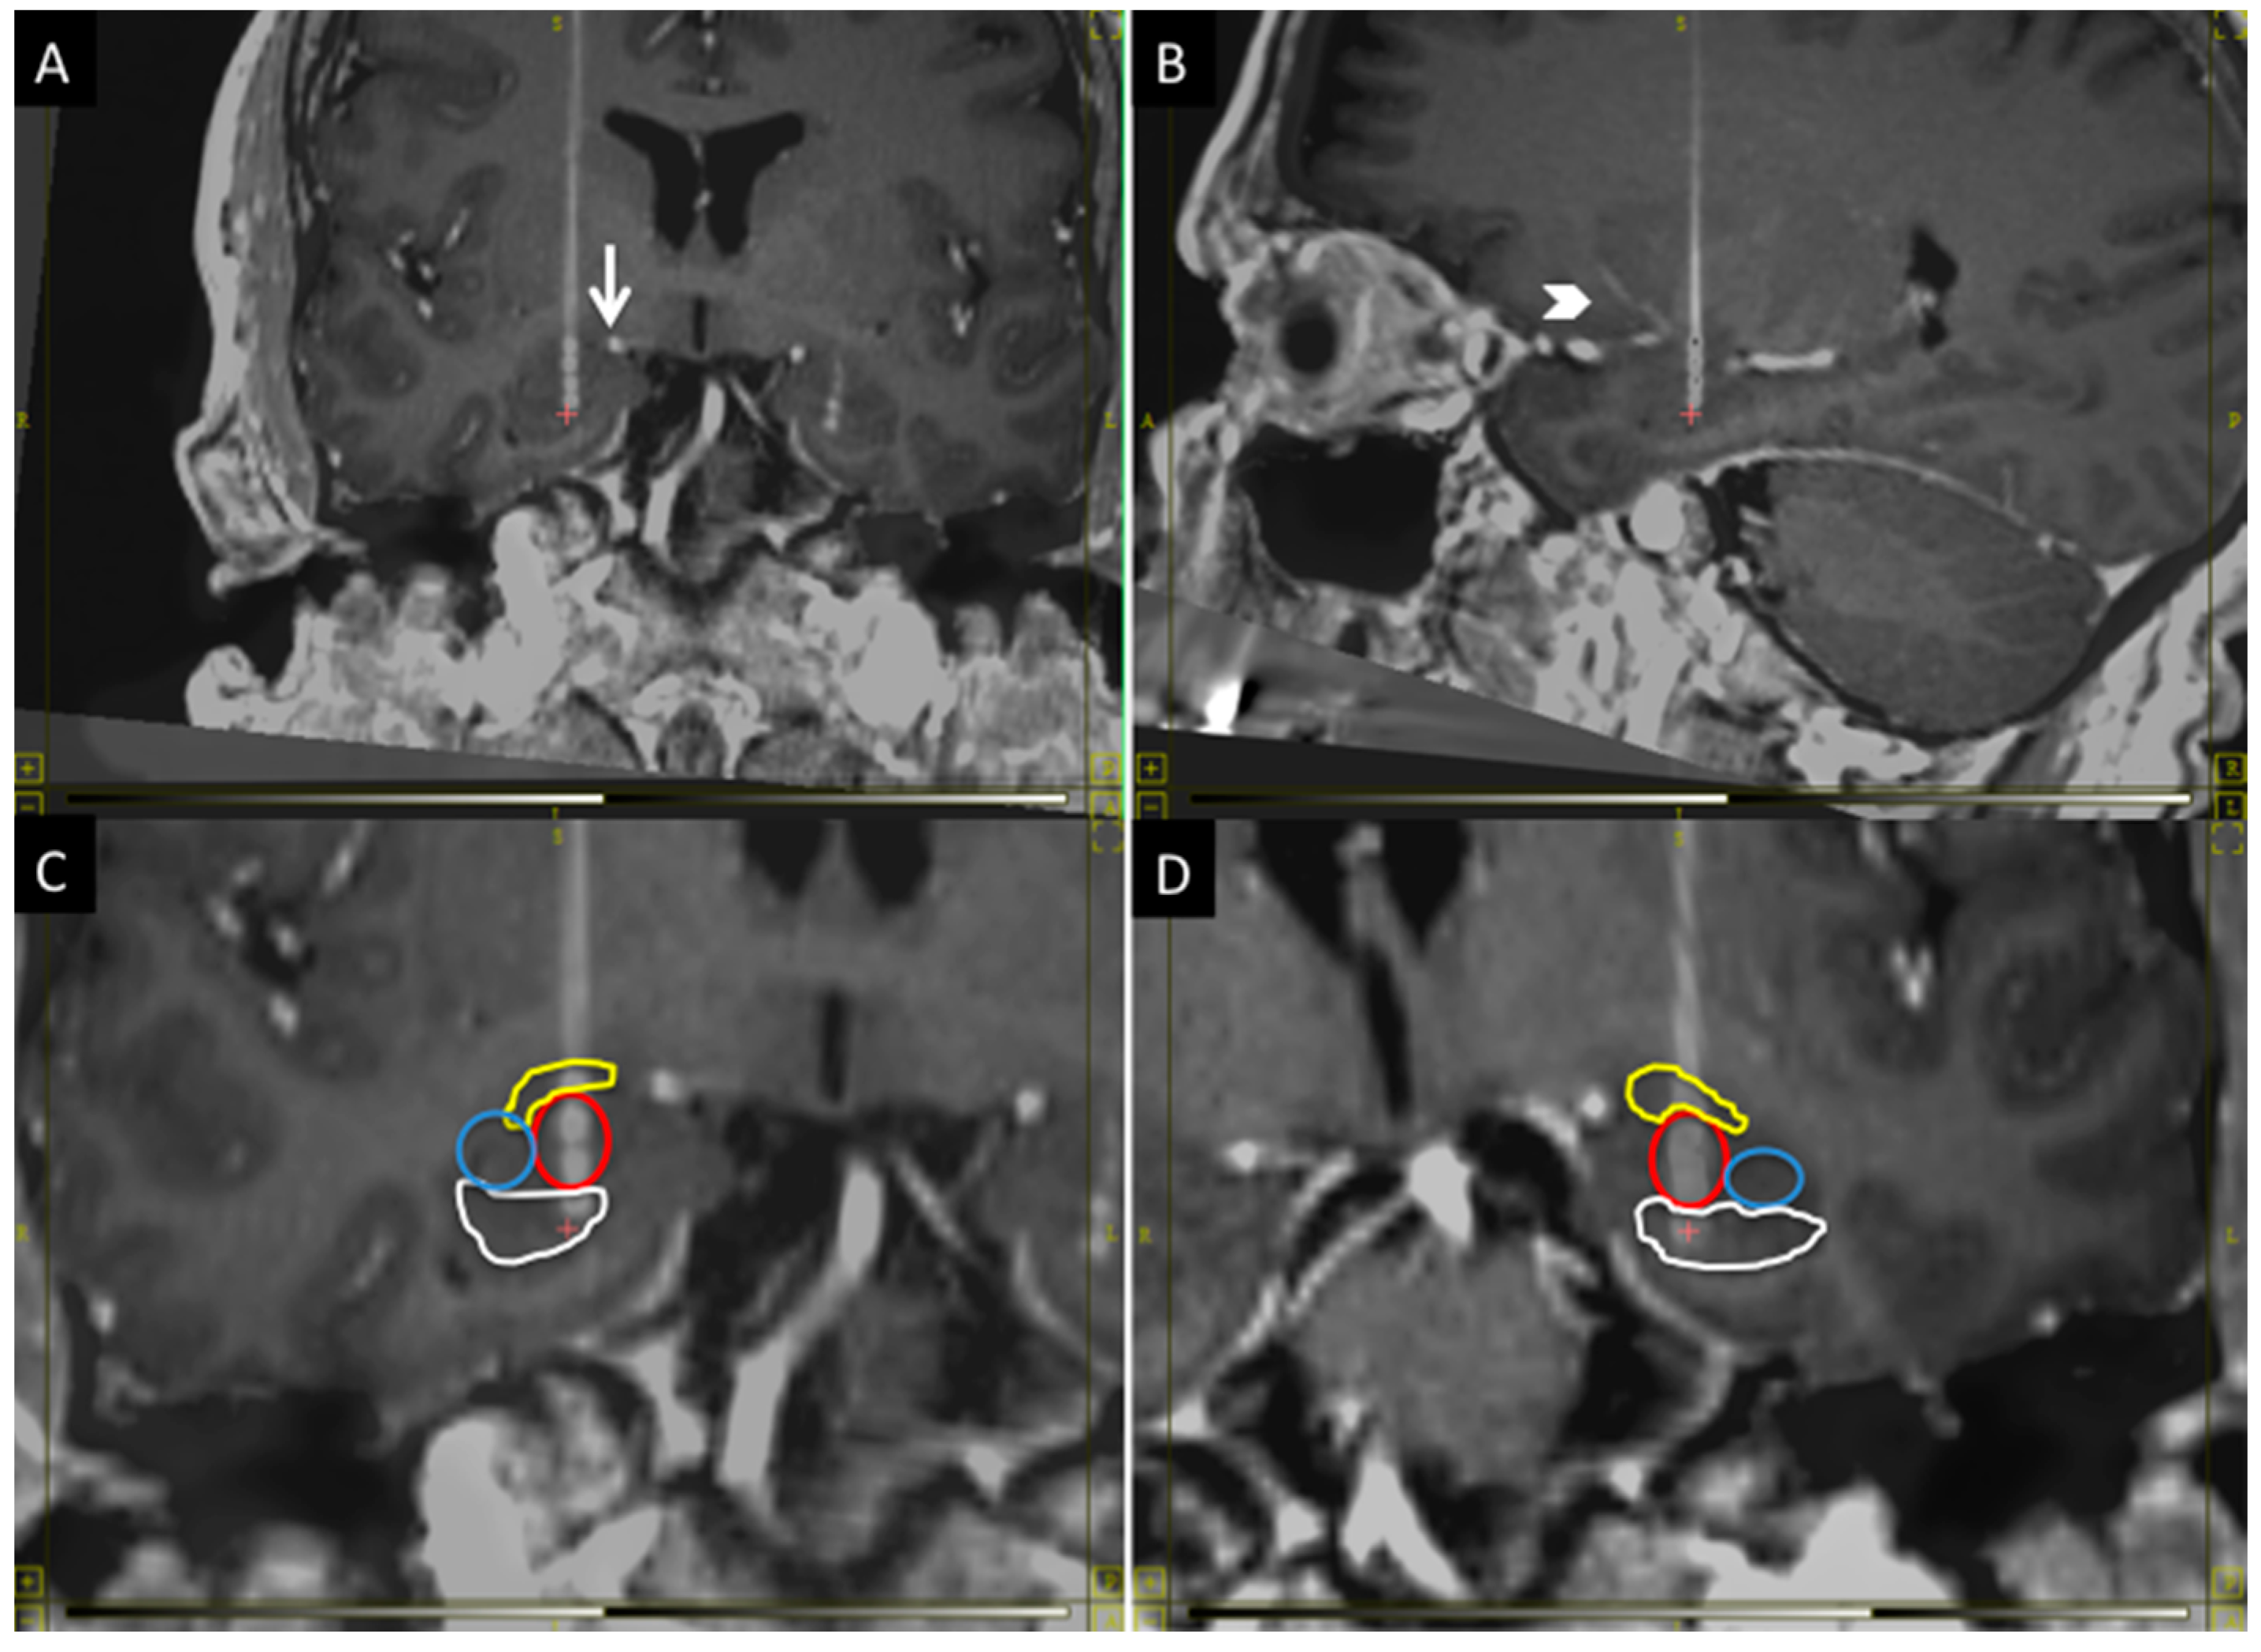

The BLn is located in the inferior portion of the amygdala. It is at the center of the amygdala where it is flanked laterally by the lateral nucleus and medially by the basomedial and basolateral ventromedial part [14]. The central and medial nuclei of the amygdala are dorsal to the BLn. When the MRI is oriented along the AC-PC plane, the fornices can be seen crossing the hypothalamus in the same coronal plane as the BLn within the amygdala [14]. Within this coronal plane, the BLn is located in the center of the amygdala from a medial-to-lateral perspective. When studying the axial plane at this level, the BLn is located just anterior to the tip of the temporal horn, which thus serves as another important landmark [11]. Finally, the inferior border of the BLn is marked by the presence of the head of the hippocampus (Figure 1).

Figure 1.

The figure shows the anatomical position of the BLn electrodes in the coronal plane (A,C,D) and sagittal plane (B): (A) The electrode must avoid the superior extent of the ambient cistern (arrow); (B) and the lenticulostriate vessels (arrowhead); (C,D) respectively show the right and left Bln electrodes with segmentation of the nuclei: in yellow, the central nucleus; in red, the basolateral nucleus; in blue, the lateral nucleus and, in white, the head of the hippocampus. The electrode contact distribution, from dorsal to ventral: Central nucleus (one contact); BLn (two contacts); Hippocampus (one contact). Laterally: Lateral nucleus (zero contacts).

The electrode trajectory must avoid critical structures to permit a safe transfrontal approach. It should be posterior to the lenticulostriate perforator vessels from the first segment of the middle cerebral artery and it should remain lateral to the superior aspect of the ambient cistern (Figure 1). Finally, the trajectory should be seen traversing just anterior to the tip of the temporal horn to confirm the location within the BLn [11]. The location of the entry point will vary depending on the anatomy of the critical structures. In general, it will have a lateral angle of 0–10° from midline and an anterior angle of 70–80° from the AC-PC plane.